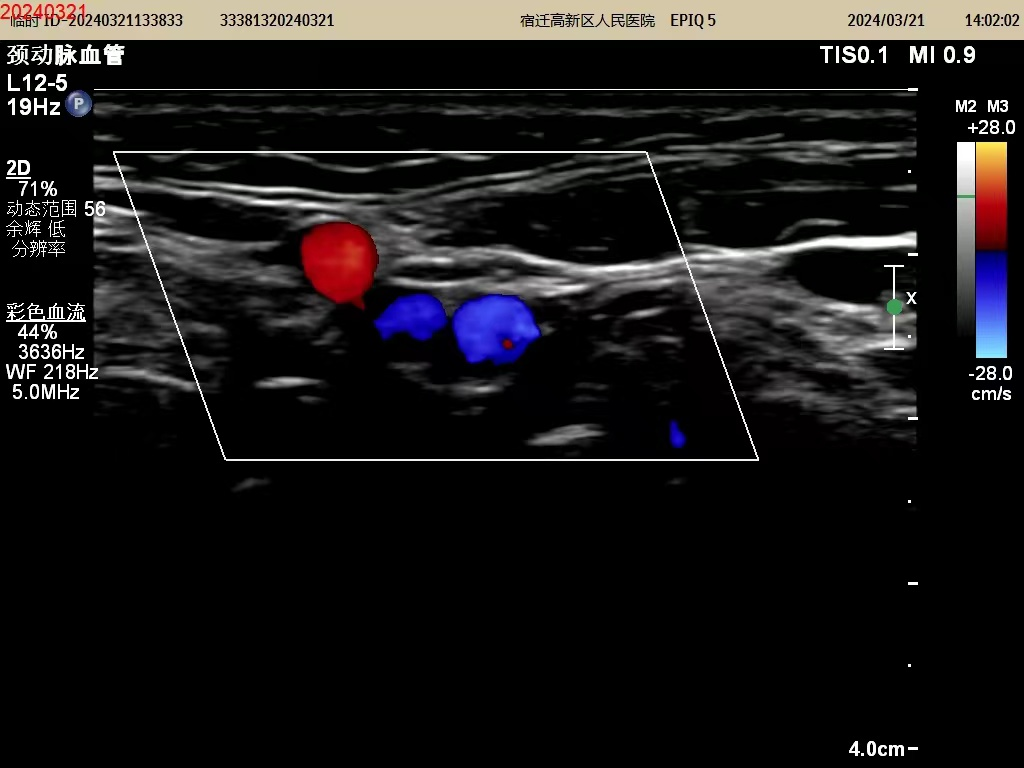

彩超又称“彩色多普勒超声”,它是在灰阶超声的基础上利用了多普勒原理,实现了彩色血流显像,是对血流的方向做判断。所以只有在观测血流的时候,才会在屏幕上看到红色或蓝色的彩色信号,而不是像我们大家所认为的像彩色电视一样的满屏彩色信号。